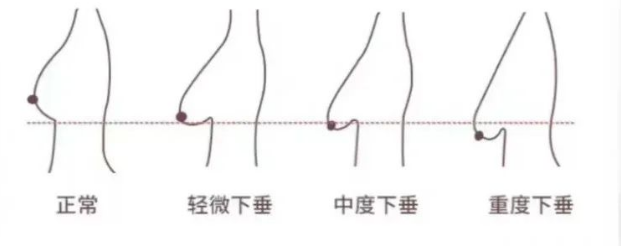

只要有受到地心引力➕年龄增长,下垂可以说是不可逆的,只是垂的组织相对少,视觉上严重程度不如大胸明显~所以,既然这是有胸人类都会出现的问题,我们也不用过度焦虑~可以先自测下是否有下垂情况????

✅乳头向上的,说明乳房形态健康;❌乳头有低于下皱壁的趋势,或已低于下皱壁,那就是出现了下垂的情况。